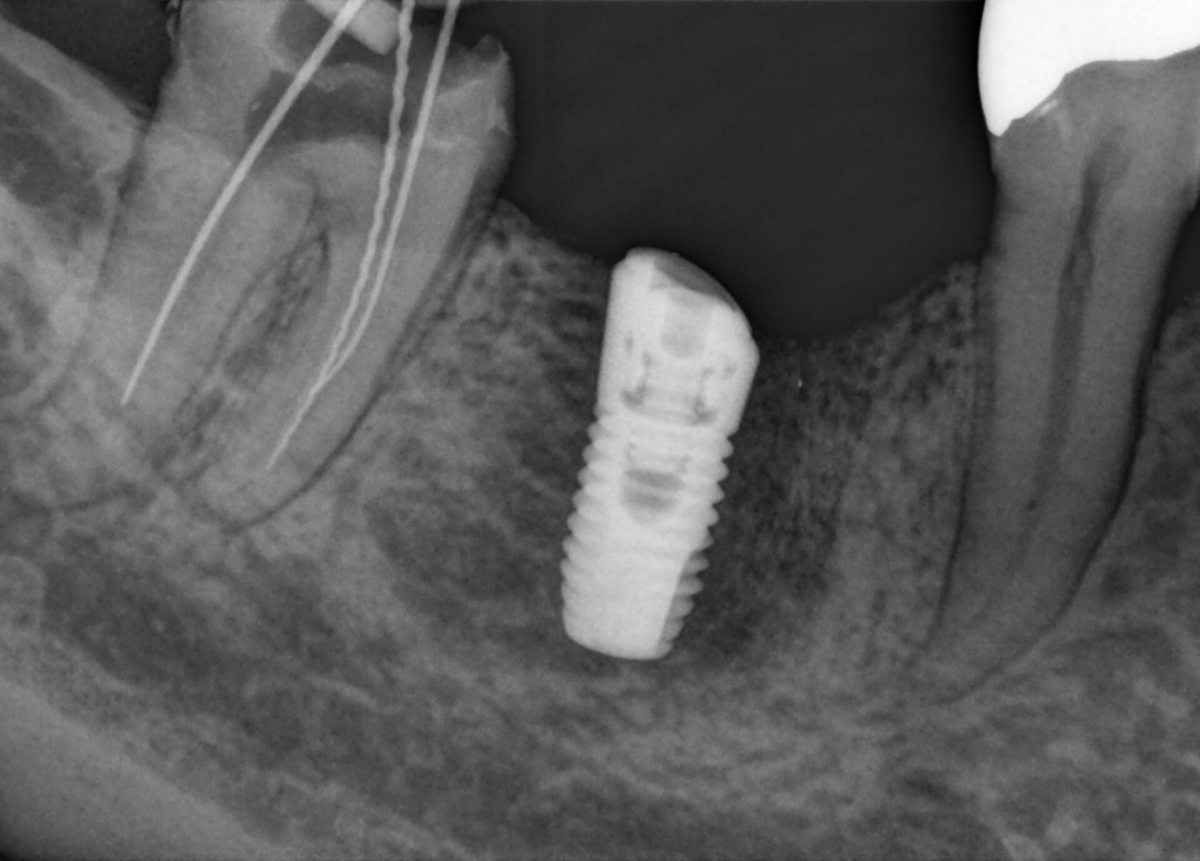

MARS – software pro redukci kovových artefaktů

Kovové artefakty jsou ve 3D rentgenovém zobrazování výzvou. RTG-kontrastní objekty vytvářejí během trojrozměrné rekonstrukce stíny a šmouhy a tím narušují výsledný snímek. MARS automaticky redukuje kovové artefakty a usnadňuje stanovení diagnózy.

Porovnání snímků "S" a "BEZ" použití softwaru MARS